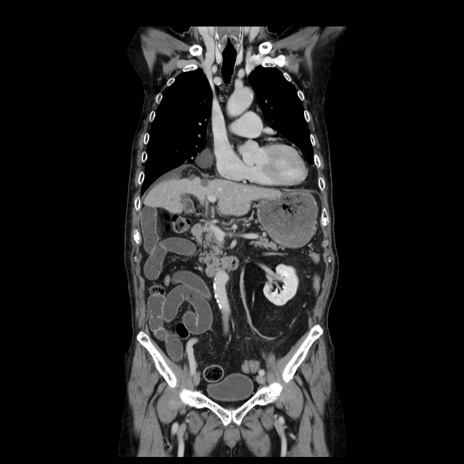

症例21(冠状断像)

【症例】70歳代男性

【主訴】腹痛

【現病歴】肝硬変・肝細胞癌にてかかりつけの方。約9時間前に食後より腹痛出現。症状が徐々に増悪し、嘔吐出現したため来院。

【既往歴】肝硬変、肝細胞癌(RFA、TACE後)

【身体所見】意識清明、表情苦悶様、BT 36℃、BP 129/78mmHg、P 88bpm、SpO2 97%(RA)、右上腹部から心窩部にかけて圧痛あり、反跳痛なし、筋性防御あり。

【データ】WBC 5800、CRP 0.16